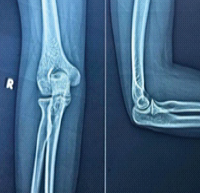

The patient was placed in a thumb spica slab immediately after surgery for 2 weeks to provide immobilization and reduce stress on the surgical site. Post that sutures were removed and a thumb spica cast was applied for 6 weeks. During follow-up visits at 3 and 6 weeks, X-rays were done, which showed satisfactory graft positioning and bone healing. After 6 weeks, the cast was removed, and gradual mobilization of the interphalangeal (IP) joint and wrist joint was started. By 12 weeks, X-rays showed complete consolidation of the graft with endplates, and K-wires were removed (Fig. 5). Physiotherapy was advised for metacarpophalangeal and IP joints. The patient had regained functional use of his thumb with significantly improved range of motion (ROM), stable grip, and adequate pinch strength by 18 weeks.

Figure 5: (a and b) Immediate post-operative X-rays, (c and d) follow-up X-rays at 12 weeks, (e and f) post-K-wire removal X-rays, (g-i) 18 weeks range of motion clinical pictures.